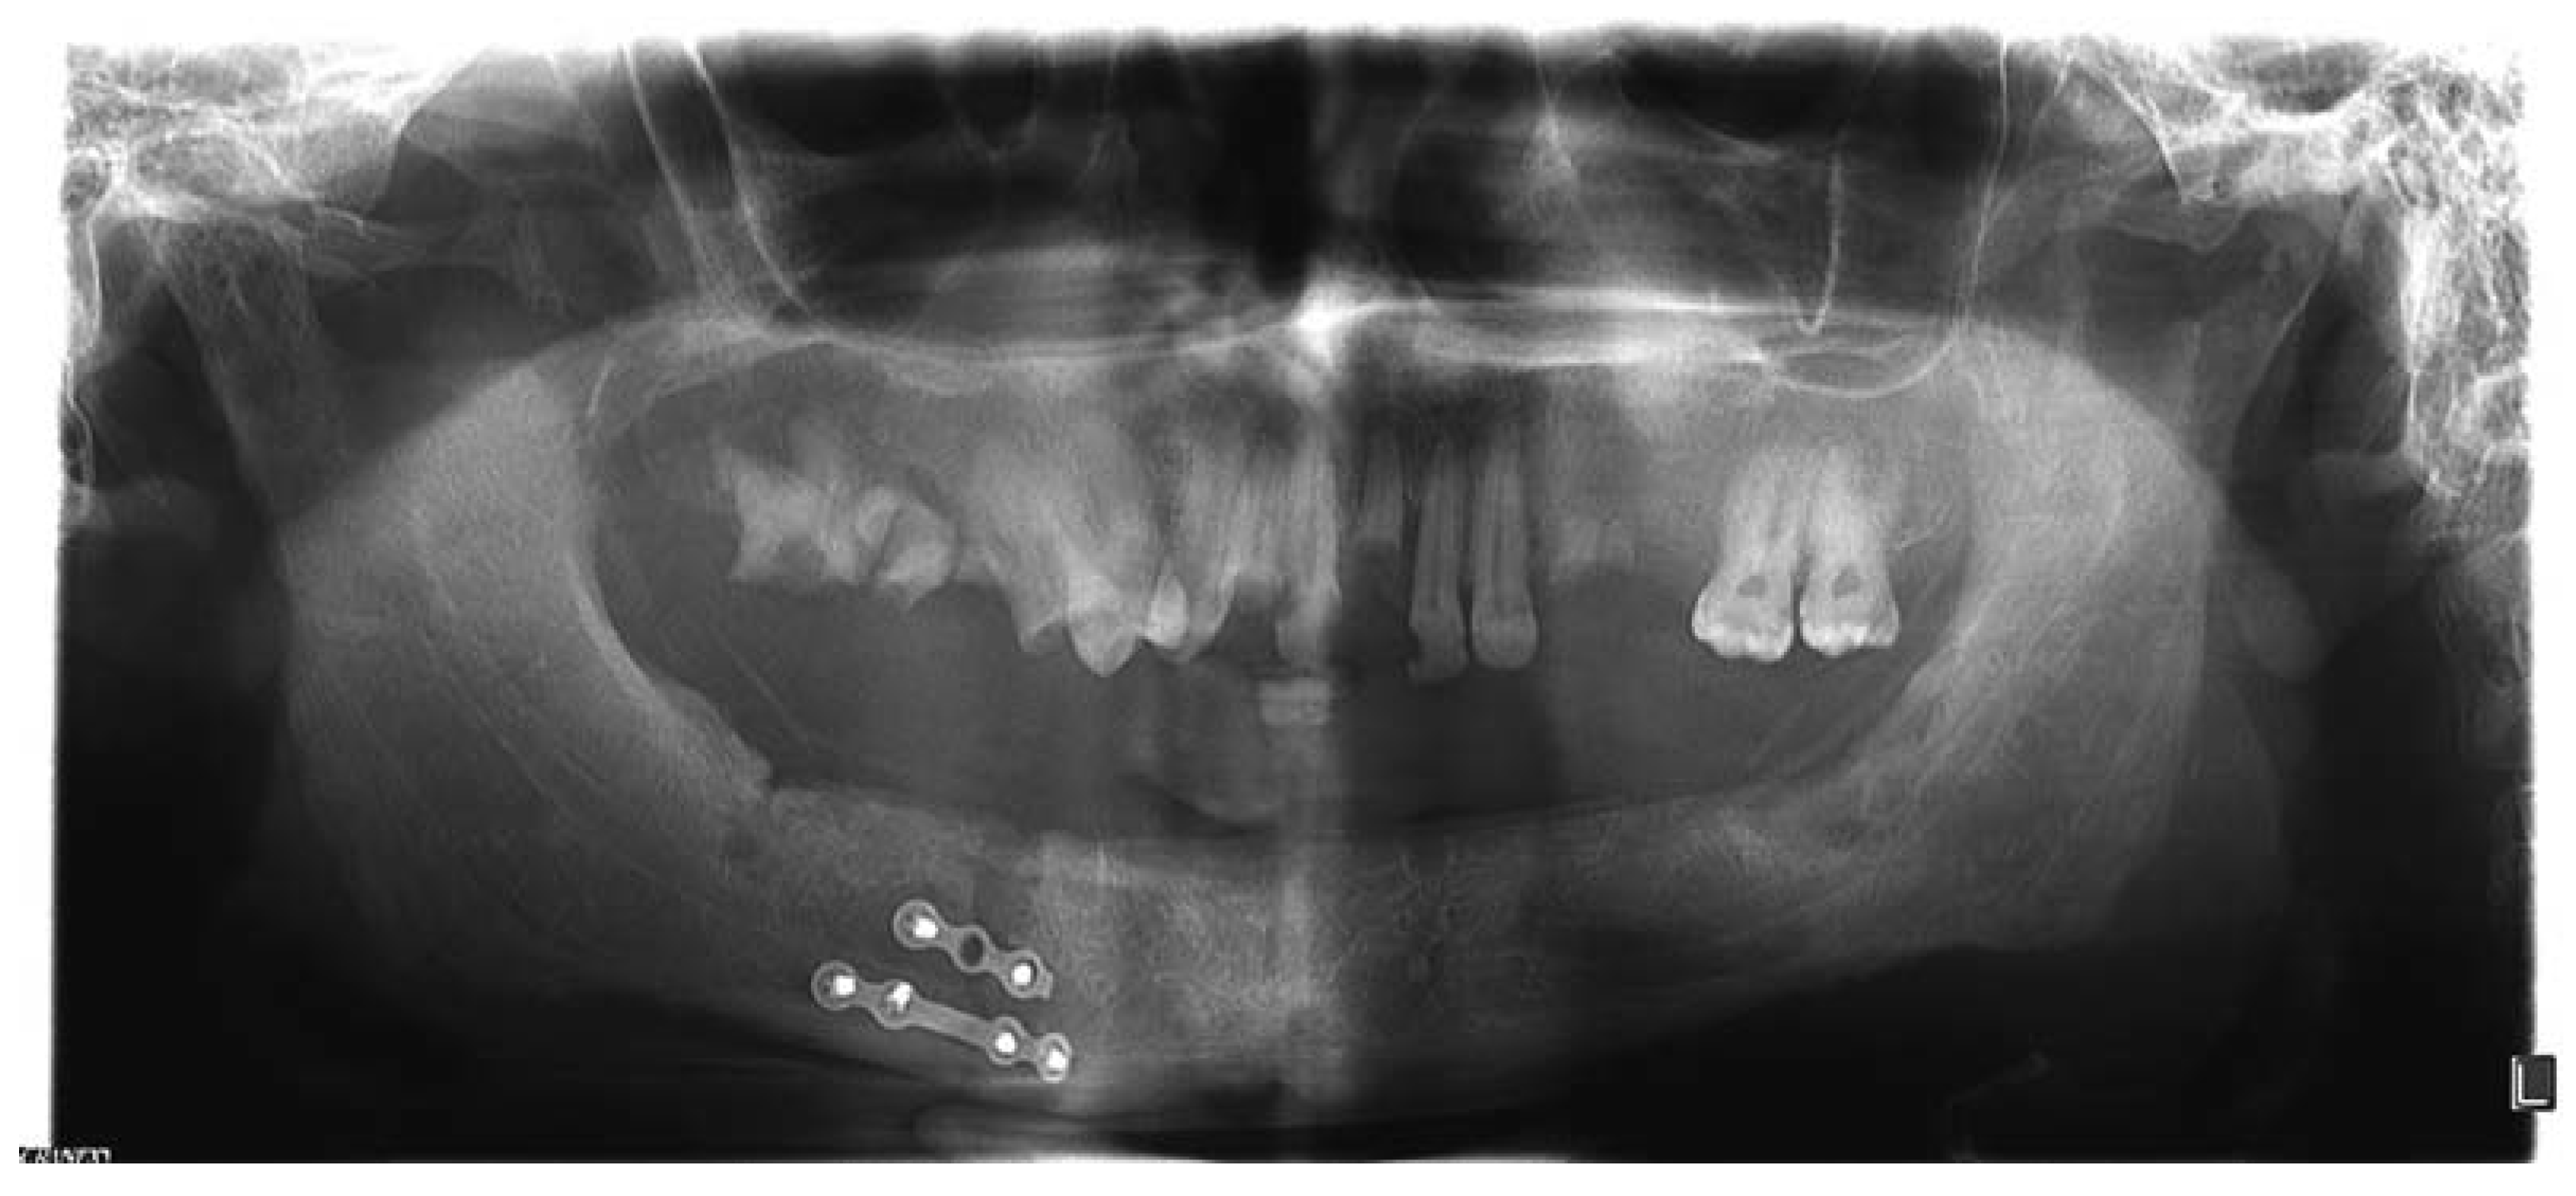

:Case Presentation